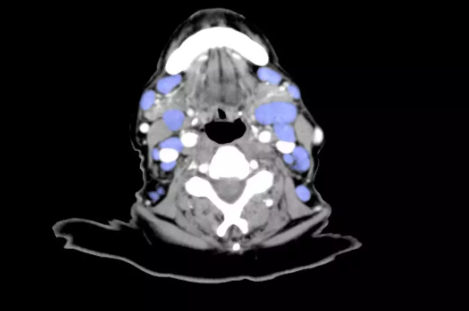

如果孩子的淋巴結腫大,你有可能能夠摸到或看到腫大的淋巴結。它們也可能有觸痛。一般來說,當觀察腫大的淋巴結周圍組織時,都可能發(fā)現(xiàn)存在被感染的癥狀或損傷,正是它們引起了淋巴結腫大。例如咽喉痛有可能引起頸部淋巴結腫大,或者胳膊上的感染有可能引起腋窩淋巴結腫大。有時候,全身性的疾病(病毒引起的)有可能導致身上很多部位的淋巴結都出現(xiàn)輕微腫大。總的來說,因為孩子比成年人更容易被病毒感染,他們的淋巴結,特別是頸部淋巴結的腫大更常見。頸部、鎖骨上的淋巴結腫大可能是由于感染引起的,有時候甚至表明存在腫瘤,所以應該盡快讓醫(yī)生為孩子做一次詳細的檢查。

對絕大多數(shù)病例來說,淋巴結腫大都不是非常嚴重的疾病。淋巴結的腫大一般會在原發(fā)病痊愈后消失。通常來說,淋巴結都會在幾周后恢復正常。如果孩子出現(xiàn)了下述情況,應該及時就診:

治療淋巴結腫大的方法取決于其原發(fā)病的病因。如果腫大的淋巴結附近的皮膚或組織被某種細菌感染了,使用抗生素控制感染后,淋巴結就可以逐漸恢復正常大小。如果是淋巴結本身發(fā)生感染,可能不僅需要抗生素治療,還需要局部熱敷以限制感染蔓延,接下來用外科手術的方法引流出膿液。如果做了引流,引流物需要在培養(yǎng)基中培養(yǎng),使醫(yī)生判斷引起感染的原因,從而選擇最適合的抗生素。

如果兒科醫(yī)生不能確定引起腫脹的病因,或者如果在抗生素治療之后淋巴結腫大并沒有好轉,就需要做進一步的檢查。舉例來說,如果孩子出現(xiàn)發(fā)熱以及嚴重的咽喉疼痛(但不是鏈球菌性的)、身體虛弱、淋巴結腫大(但是沒有發(fā)紅、發(fā)熱及觸痛),病因就有可能是傳染性單核細胞增多癥,盡管這種疾病更常見于大一點的孩子,特殊檢查可以確定診斷。對于病因不明的淋巴結腫大,醫(yī)生也有可能再為孩子做一個結核菌素實驗。

如果淋巴結不明原因的長期腫大,淋巴結活檢就非常重要(從淋巴結上取下一部分組織并放在顯微鏡下檢查)。非常少見的病例是因為存在腫瘤或感染了真菌,需要接受特殊治療。